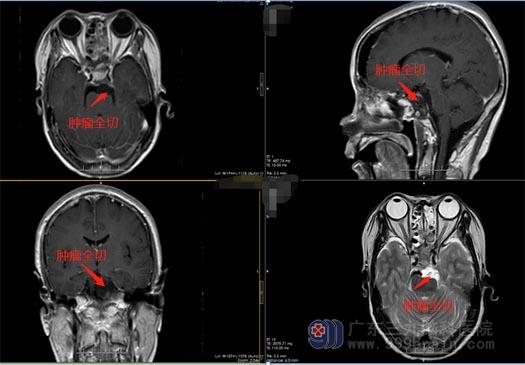

2022年1月10号,鲁明副院长带领外五科手术团队为陈阿姨施行了“全麻下行内镜经鼻上中斜坡脑膜瘤切除术+颅底重建术”。手术很成功,双侧鼻腔填塞膨胀海绵止血,病人出血约200ml,未输血。术后第一天,陈阿姨即神志清醒、四肢活动正常,复查头颅肿瘤全切,未见颅内出血;1月21日顺利出院。